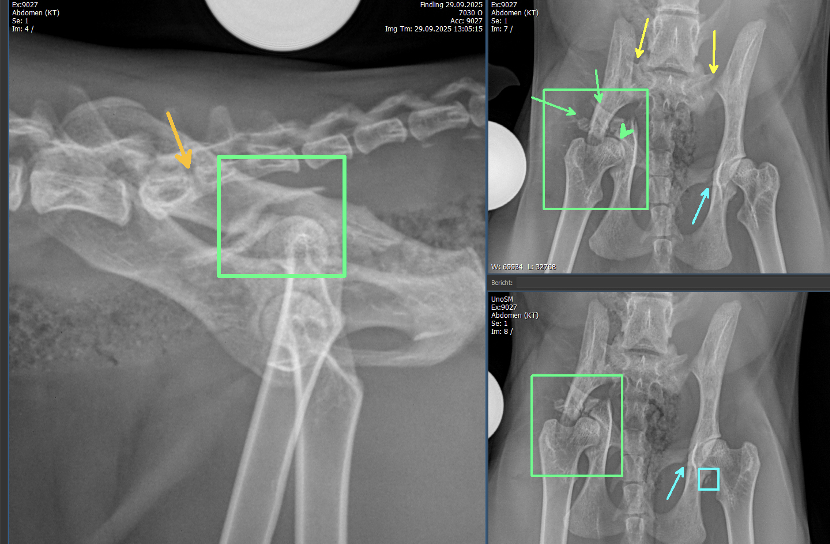

Mehrfrageant-Fraktur am rechten Acetabulum. Zum einen besteht am rechten Acetabulum eine Mehrfrageant-Fraktur mit sicherer Beteiligung des Iliums (grüne Rechtecke). Die rechte Darmbeinschaufel ist nach mediokaudal rotiert, wodurch der Beckenkanal kranial des Acetabulums erweitert erscheint. Zusätzlich besteht eine kaudale, sowie minimal dorsale Verschiebung der Darmbeinschaufel, wodurch in der ventro-dorsalen Aufnahme der Trochanter major überlagert wird. Kranio-lateral des rechten Aceatbulums sind mindestens zwei längliche, teils scharfrandige, teils geringgradig irreguläre Knochenfragmente erkennbar (grüne Pfeile). Das Acetabulum selbst ist, soweit beurteilbar, artikuliert mit dem Femurkopf. Eine Beteiligung des rechten Os pubis kann aufgrund der Überlagerung nicht ausgeschlossen werden. Der Gelenkspalt ist jedoch gering- bis mittelgradig erweitert (grüner Pfeilkopf).

Iliosakrale Gelenksluxation: Linksseitig besteht zudem eine iliosakrale Gelenksluxation, wodurch das Becken nach kranioventral verschoben ist und eine geringgradige linksseitige latero-kaudale Rotation entsteht (gelbe Pfeile). Das rechte Iliosakralgelenk ist fraglich subluxiert.

Transversale Fraktur: Eine transversale, minimal irreguläre, vollständige Fraktur ist am lateralen Aspekt des linken Os pubis erkennbar (blaue Pfeile). Diese resultiert in keiner nennenswerten Knochendeviation. Am kaudolateralen Rand des linken Acetabulums befinden sich multiple kleine Fragmente (blaues Rechteck). Im umliegenden Weichteilgewebe ist weder freies Gas erkennbar, noch besteht eine deutliche Weichteilschwellung.

Verwachsene Wirbelkörper: Der S1 Wirbelkörper ist unvollständig mit dem Wirbelkörper des S2 verwachsen (orangener Pfeil). Bilateral besteht jedoch eine Artikulationsfläche beider Ala ossis sacri.